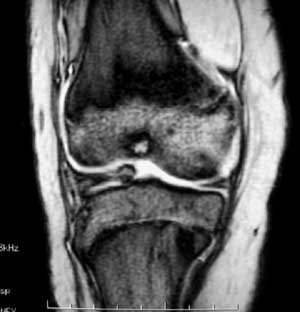

14岁女孩,7月前右膝关节疼痛,进行性加重,无外伤,无潮热盗汗,无高热,未治疗。1周前入院,下肢皮肤牵引,抗炎治疗,症状减轻。入院查右膝关节轻肿,浮膑(-),碱性磷酸酶140,余(—)。如何诊治?1周前ct 见关节面破裂,关节腔穿刺少量血性液:细胞学检查示滑膜炎改变,培养未见细菌生长。 7月前ct

6月前mri,1周前ct

考虑结核可能性大,骨样骨瘤待排;结核单关节病变好发于承重关节,髋关节、膝关节病变占80%左右,关节局部疼痛、肿胀,活动受限,起病缓慢。骨样骨瘤多发生在长骨的骨皮质,很少部分发生在骨松质,以股骨、胫骨最常见,病灶周围有显著的反应性硬化环,局部疼痛,夜间较重,近关节的病灶有关节积液。本病例应进一步做其他检查。

低毒感染,骨样骨瘤待排,mri表现整个骨够信号异常并跨够线,良性肿瘤基本排除,(但骨样骨瘤与骨母与感染有关),病灶周边硬化不是tb表现。

病变骨质增生硬化,不支持结核。mri示病变中心内短t1、长t2信号,考虑为骨样骨瘤并瘤巢内出血。

病变特点:股骨的非负重区的破坏病灶,病灶边沿的硬化明显,ct mri均显示病变为慢性过程,关节积液不明显,考虑低毒感染可能性大,请继续抗炎治疗,不除外骨样骨瘤

病变特点:病灶较小,周围硬化环厚/明显,中心ct呈透光区,mr可见液性成分;14岁小孩,骺端关节面的病变,可考虑的病变有:1/低毒力感染,嗜酸性肉呀肿,2/软骨母细胞瘤,年龄/好发部位/信号/密度均可符合诊断,唯一不支持的是病灶中心未见点状钙化或骨化影3/腱鞘囊肿4/巨细胞瘤和骨囊肿可以不考虑。

骨骺轻度水肿,近髁间凹关节面侧骨局灶性破坏,病灶边缘有较多的环形硬化,骨显著硬化是细菌性感染的特点,关节积液不明显...抗炎治疗症状减轻,考虑为低毒感染可能性大(brodie骨脓肿可能).请继续抗炎治疗